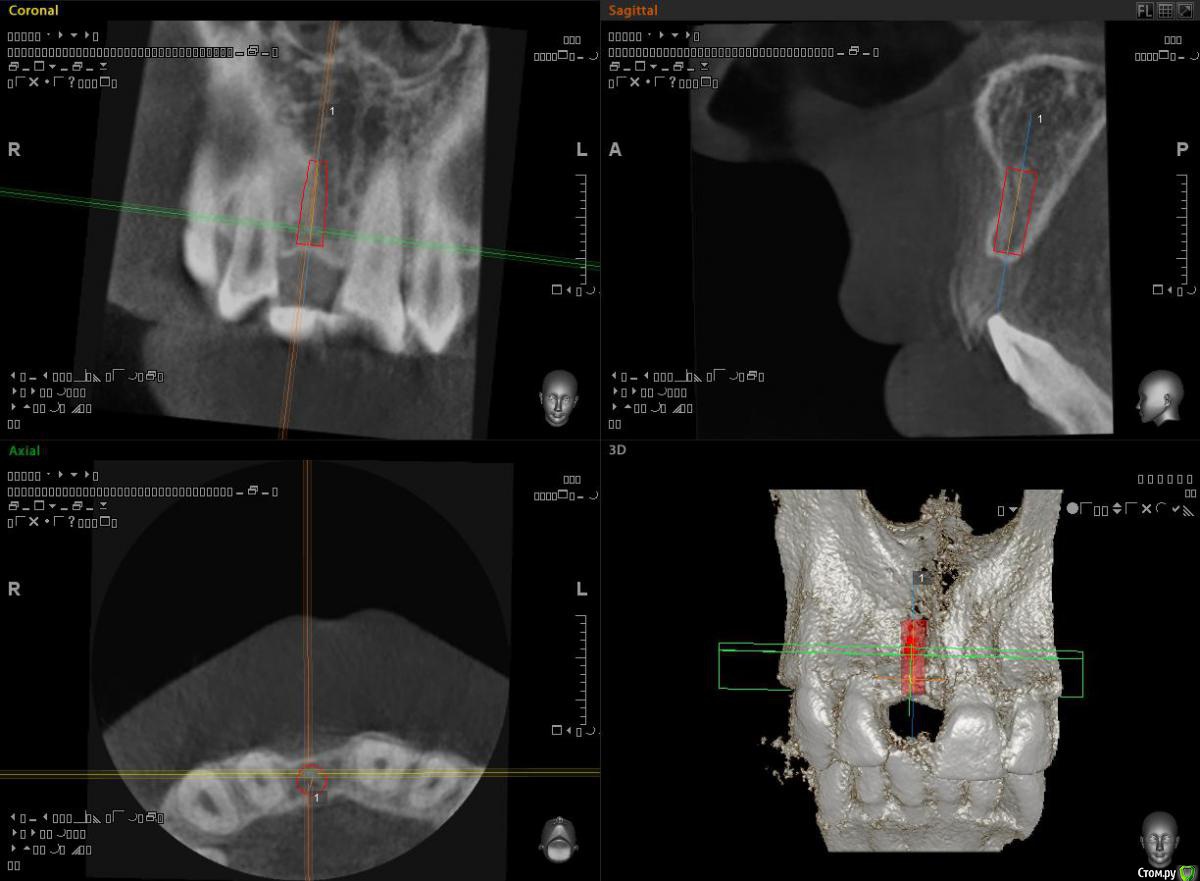

alekszander Опубликовано 11 февраля, 2016 Поделиться Опубликовано 11 февраля, 2016 (изменено) Какую лучше выбрать НКР?Первая мысль - одномоментно имплант + "сосидж".Вторая блок.Ламинат, но нечем сделать забор трансплантата.Мягкотканная только, но как-то не айс...Прошу совета, дабы понять возможность наименьшей инвазии. Изменено 11 февраля, 2016 пользователем alekszander Ссылка на комментарий

andr99 Опубликовано 11 февраля, 2016 Поделиться Опубликовано 11 февраля, 2016 Присоединюсь к krikov'у и carloss'у.Расщепленный лоскут + ССТ, возможно с остеотомами.Какой диаметр имплантата на КТ? 1 Ссылка на комментарий

alekszander Опубликовано 12 февраля, 2016 Автор Поделиться Опубликовано 12 февраля, 2016 Спасибо всем огромное! Будем или расщеплять или как Ильгам предложил попробую. Сделаю когда постараюсь выложить отчёт. Имплант Дентиум стоял 3.6 на 10. Ссылка на комментарий